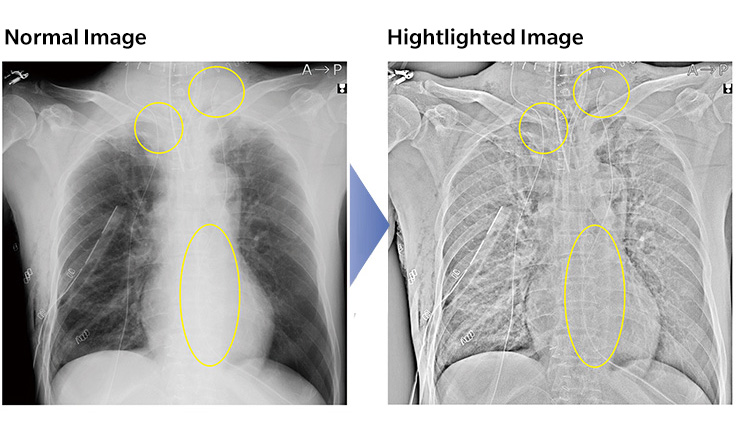

Tube and gauze image enhancement

CS-7 can highlight tube and gauze images that are difficult to be detected with normal images.

CS-7 can highlight tape and gauze images that are difficult to be detected with normal images.